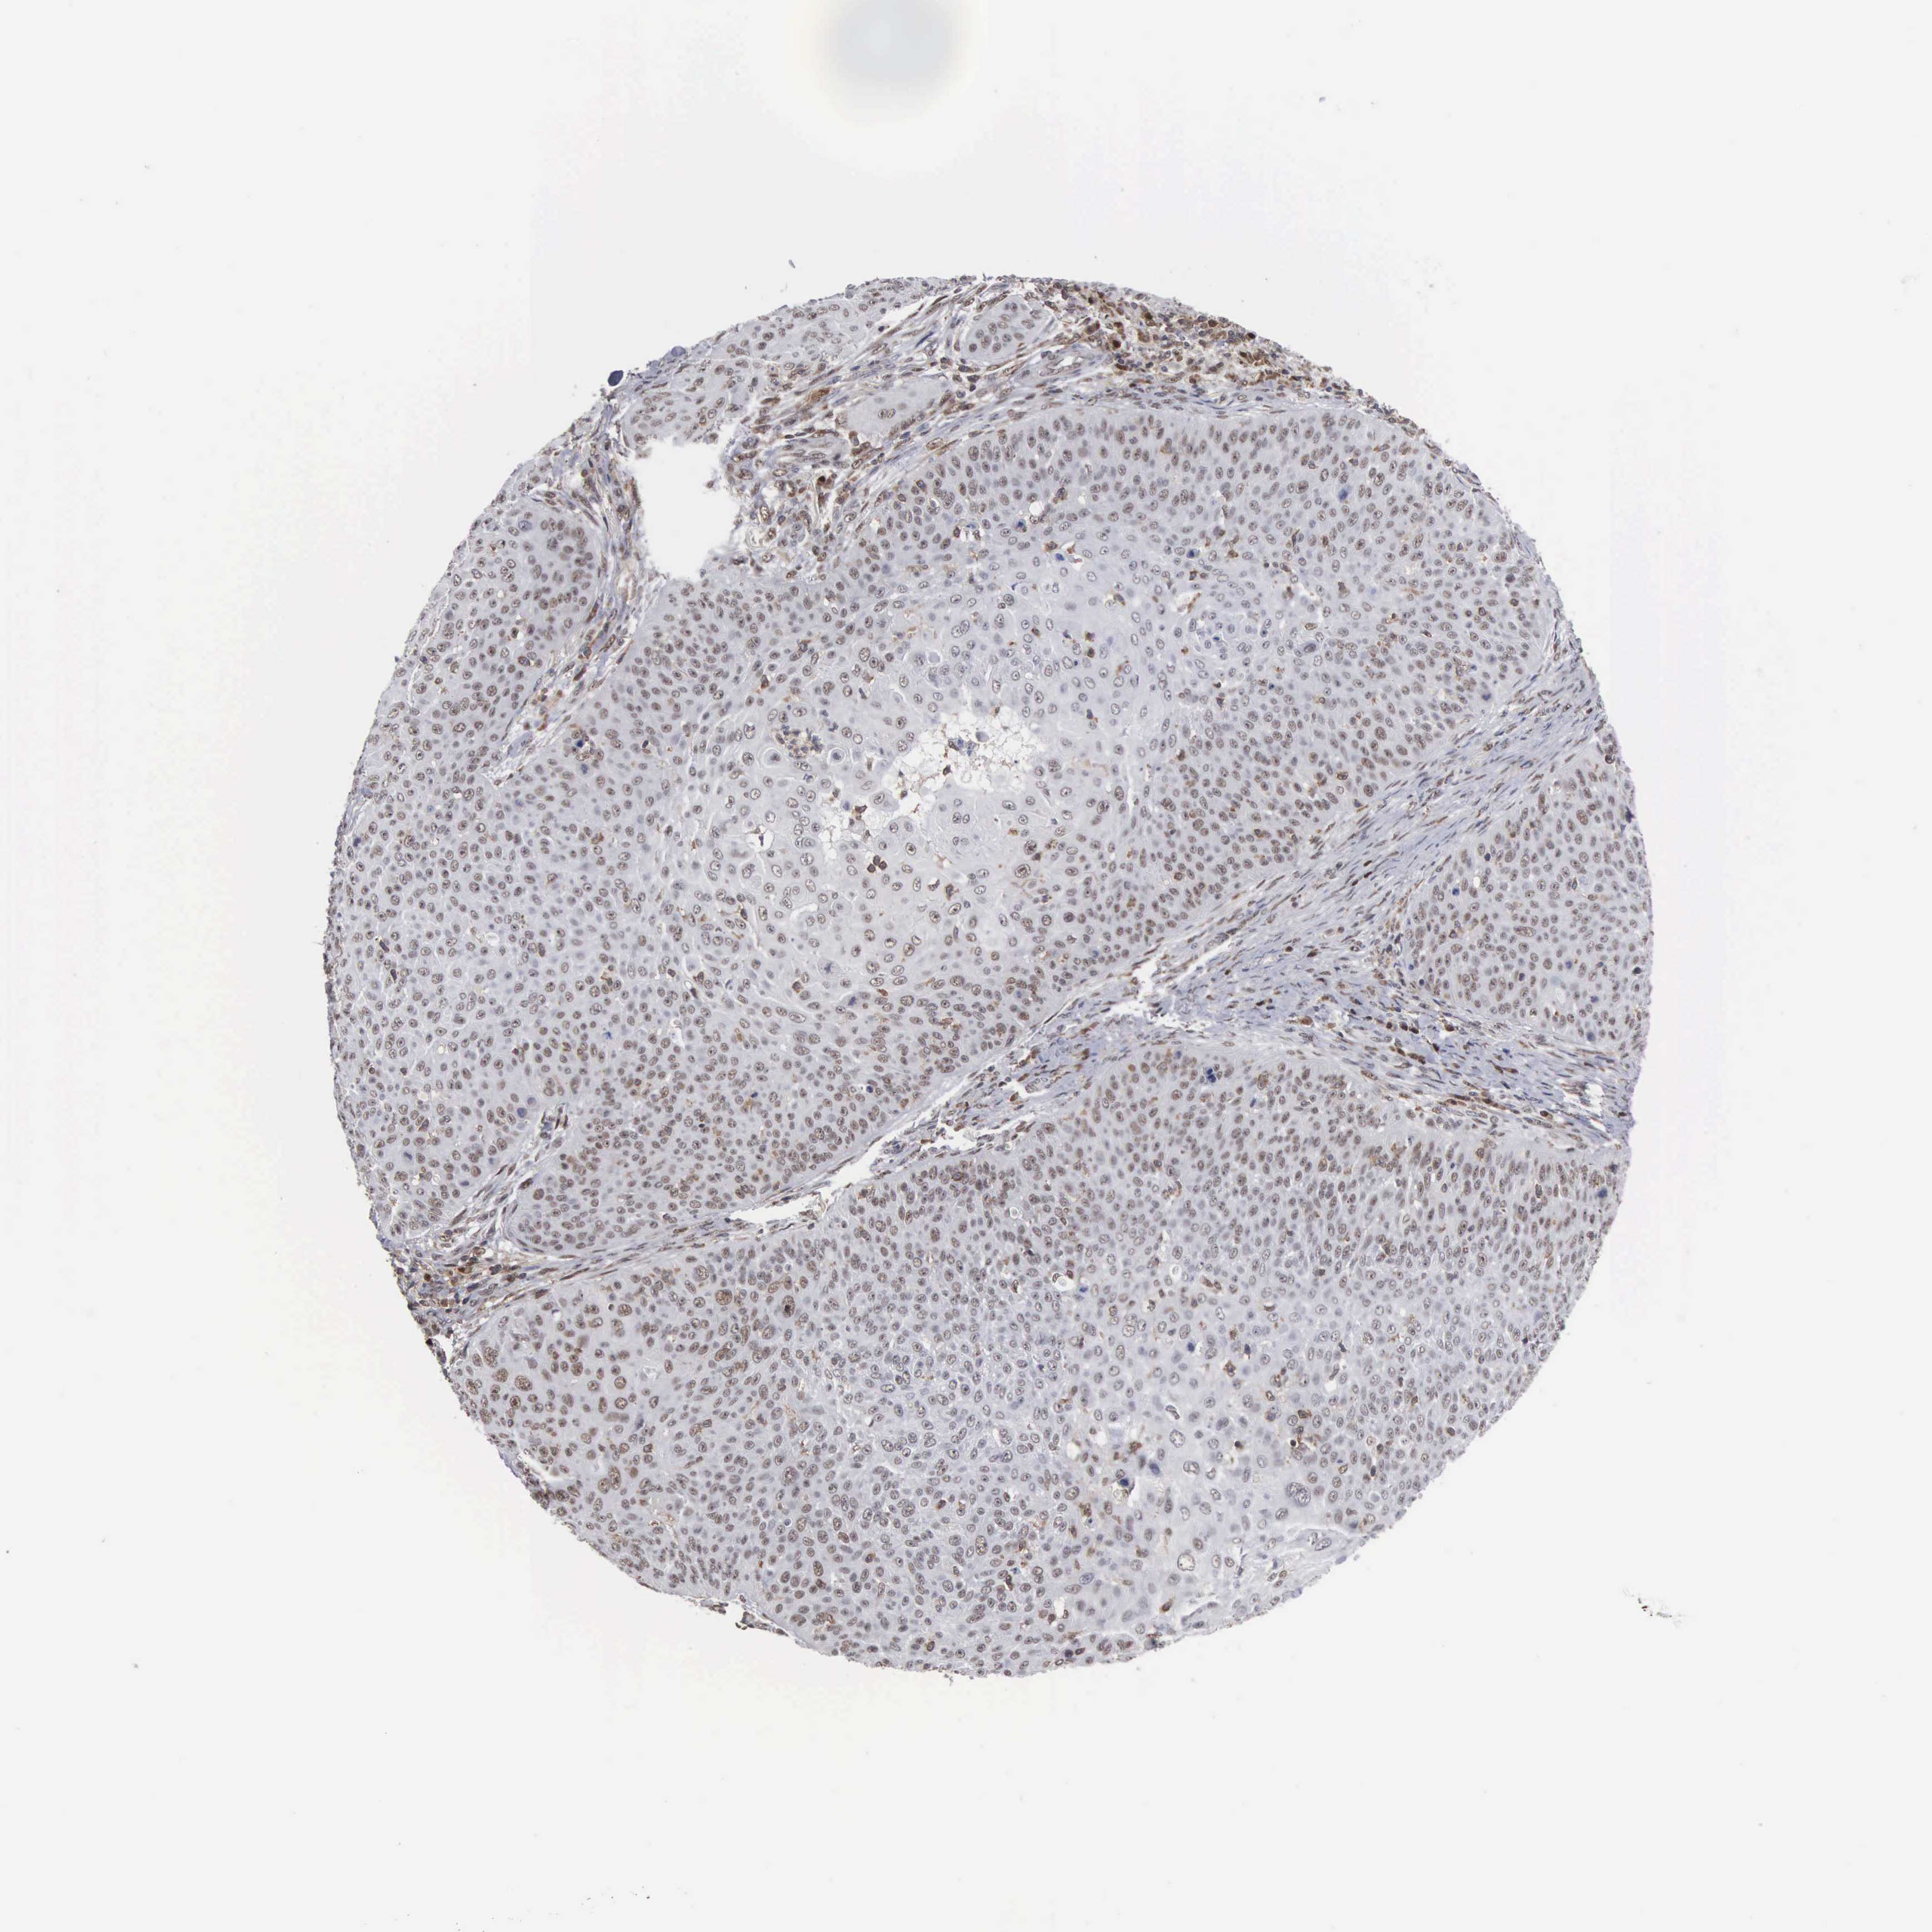

Basal cell and squamous cell cancer

SKIN CANCER - Protein expressioni

A mouse-over function shows sample information and annotation data. Click on an image to view it in a full screen mode. Samples can be filtered based on level of antibody staining by selecting one or several of the following categories: high, medium, low and not detected. The assay and annotation is described here.

Each image is clickable and will lead to virtual microscopy that enables deeper exploration of all samples and also displays staining intensity scores, fraction scores and subcellular localization as well as patient and tissue information for each sample.

Antibody HPA000943

Staining

High

Intensity

Strong

Quantity

>75%

Location

Nuclear

Squamous cell carcinoma, NOS

Basal cell carcinoma